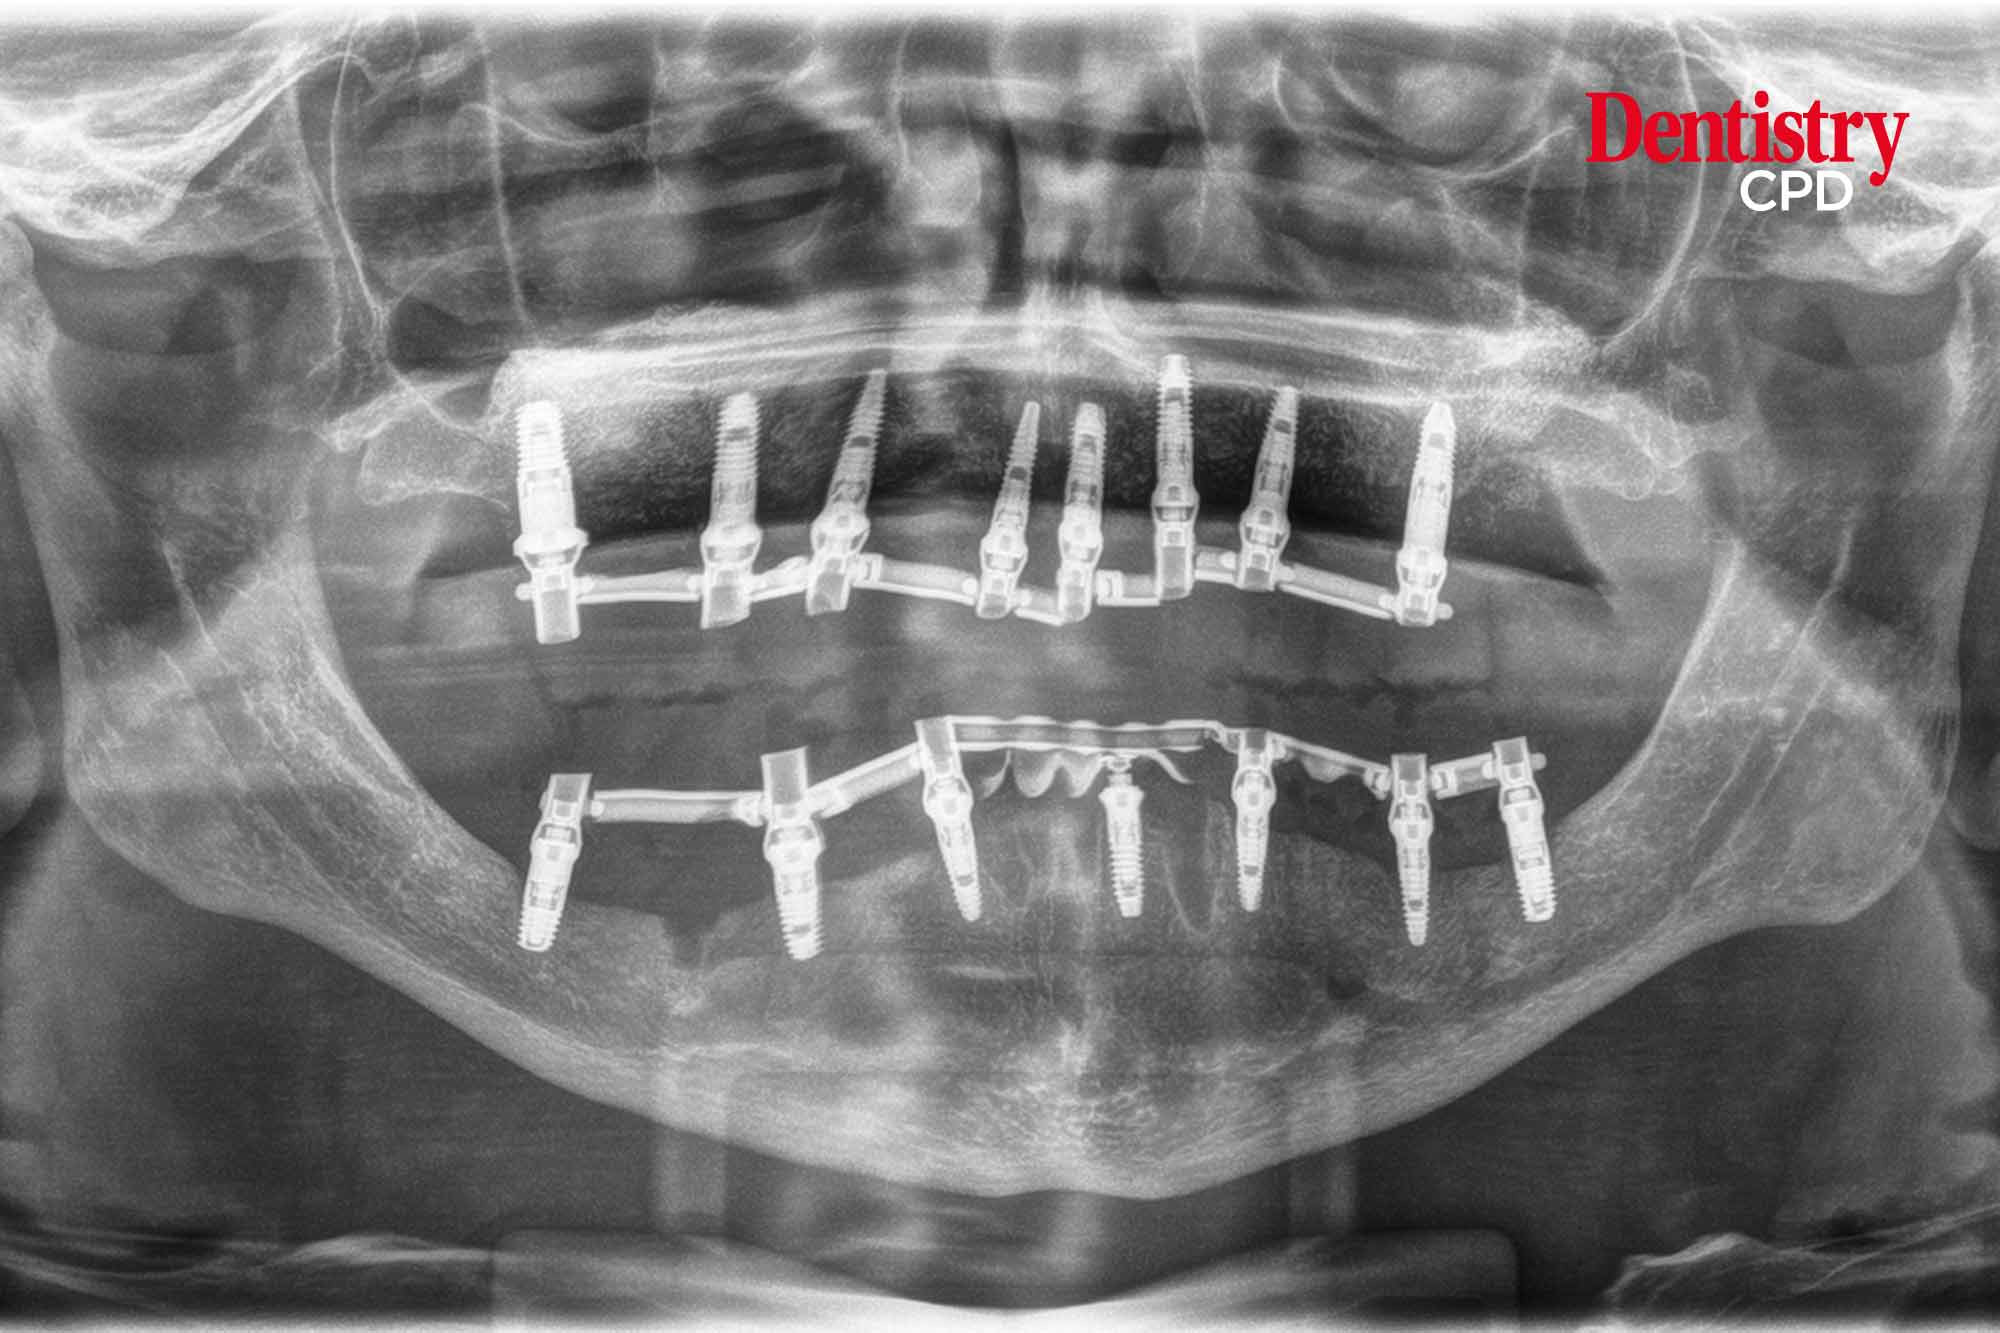

Eduardo Anitua presents the resolution of a situation of extreme bone atrophy in the horizontal direction in both the maxilla and mandible with narrow platform implants and reduced diameters.

To present a case that resolves a situation of extreme bone atrophy in the horizontal direction in both the maxilla and mandible with narrow platform implants and reduced diameters.